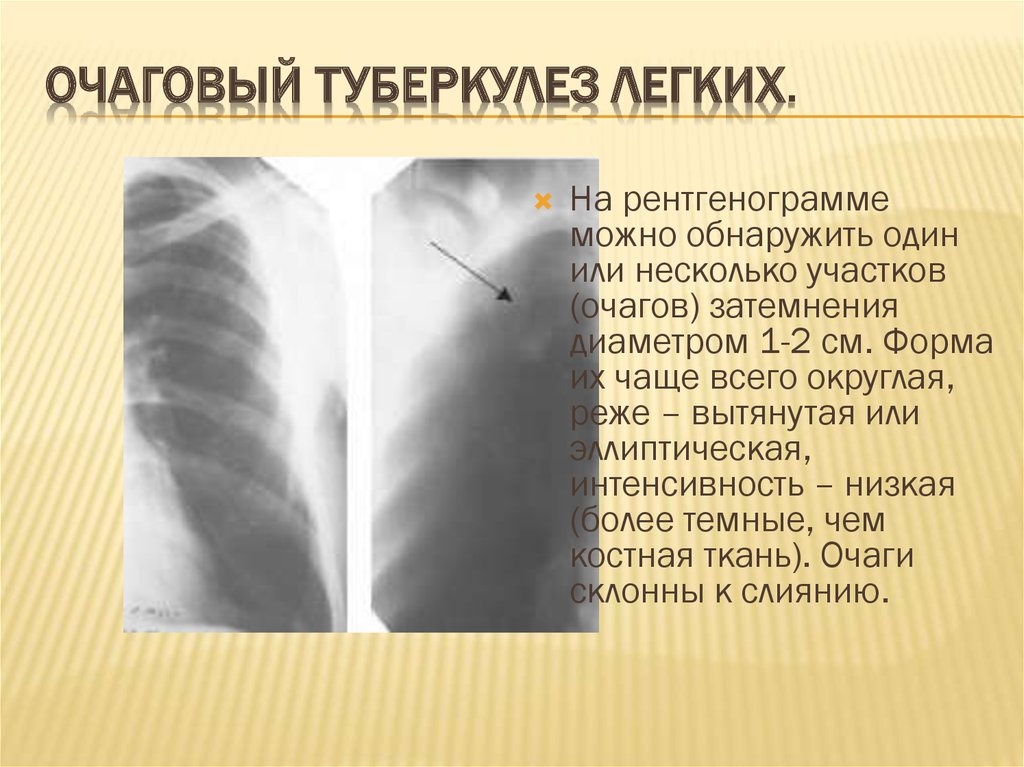

Очаговый и инфильтративный туберкулез презентация - 94 фото